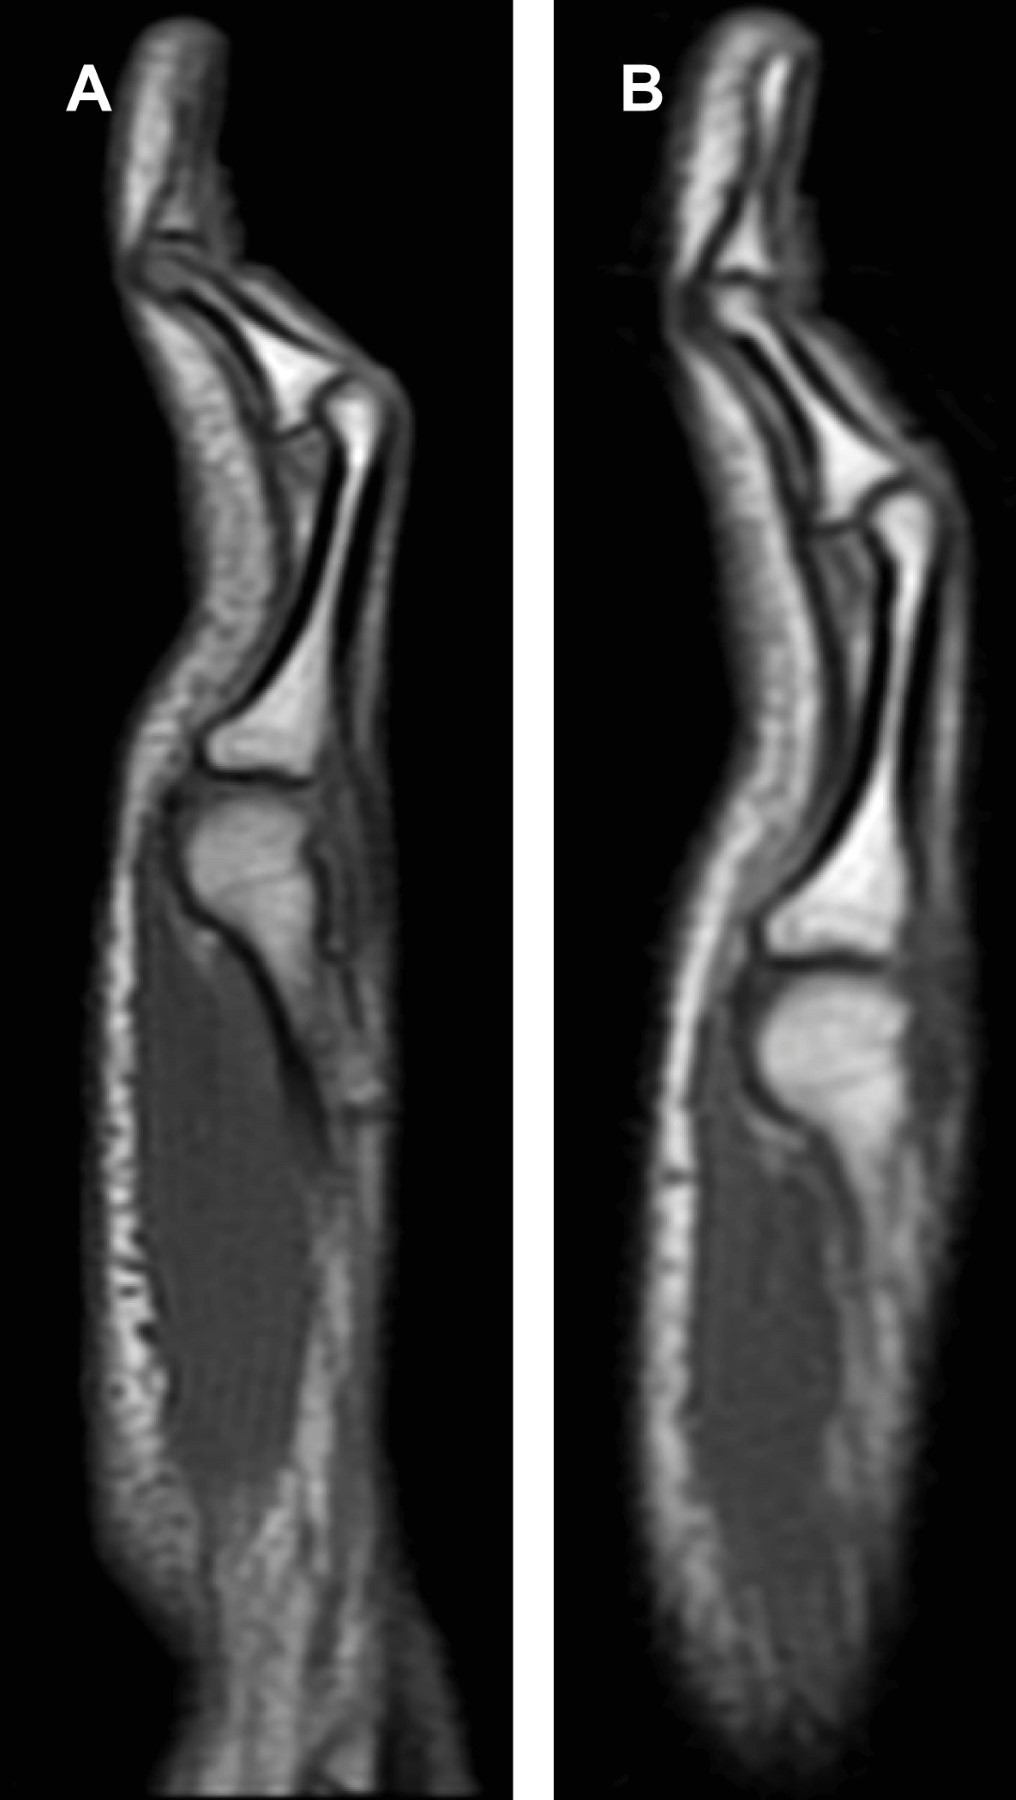

Masculino de 15 años de edad, que presenta deformidad del dedo meñique de ambas manos. No tiene antecedentes de traumatismos, patologías o síndromes congénitos. Nadie más en su familia presentaba dicha morfología en los dedos. En el estudio de resonancia magnética (RM) se observó deformidad del quinto dedo por hiperflexión de la articulación interfalángica proximal en forma bilateral (Figura 2). El vientre muscular del cuarto lumbrical presenta un curso superficial en relación a los tendones flexores superficial y profundo, secundario a una inserción anómala, con disminución en su diámetro en el plano axial (Figura 3). Todos los hallazgos son más evidentes en el dedo meñique de la mano derecha. Las articulaciones interfalángicas distales y metacarpofalángicas presentan hiperextensión compensatoria.

Favril y colaboradores publicaron una serie de tres casos con imágenes de RM y ultrasonido, donde identificaron que los músculos lumbricales son la principal estructura afectada. Estos músculos pueden tener una inserción aberrante hacia el tendón flexor superficial, un curso aberrante o una disminución en su grosor o longitud.1

Actualmente la RM es de gran utilidad, no sólo en la valoración de las alteraciones de los músculos lumbricales, sino también en otras estructuras relacionadas con la deformidad como los tendones flexores superficiales y profundos, la placa volar, los ligamentos colaterales y tejidos blandos superficiales.